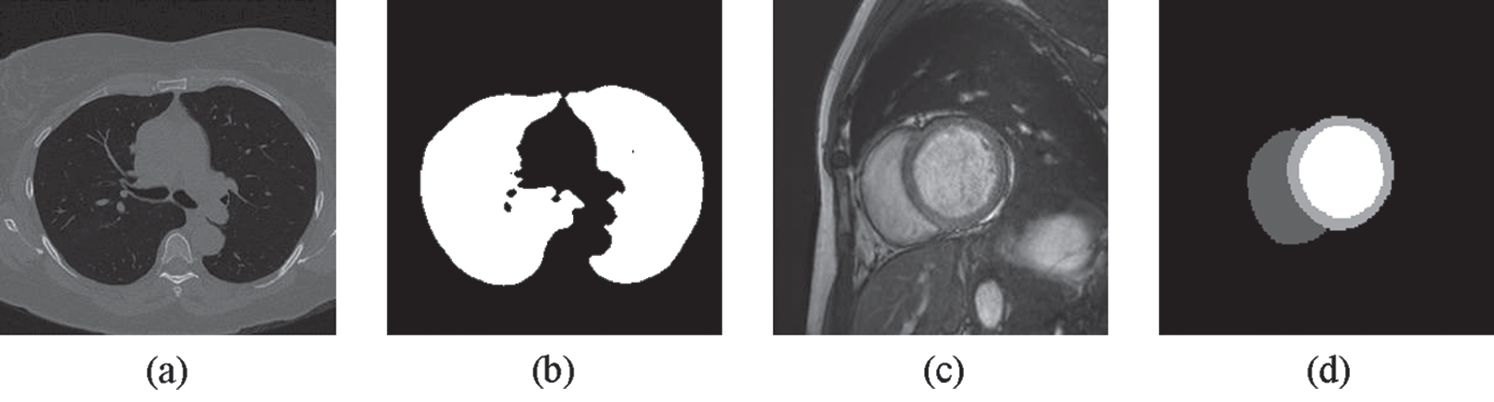

Figure 4: Examples of (a) a lung image (b) its lung mask (c) a cardiac image and (d) its LV, RV and MC masks